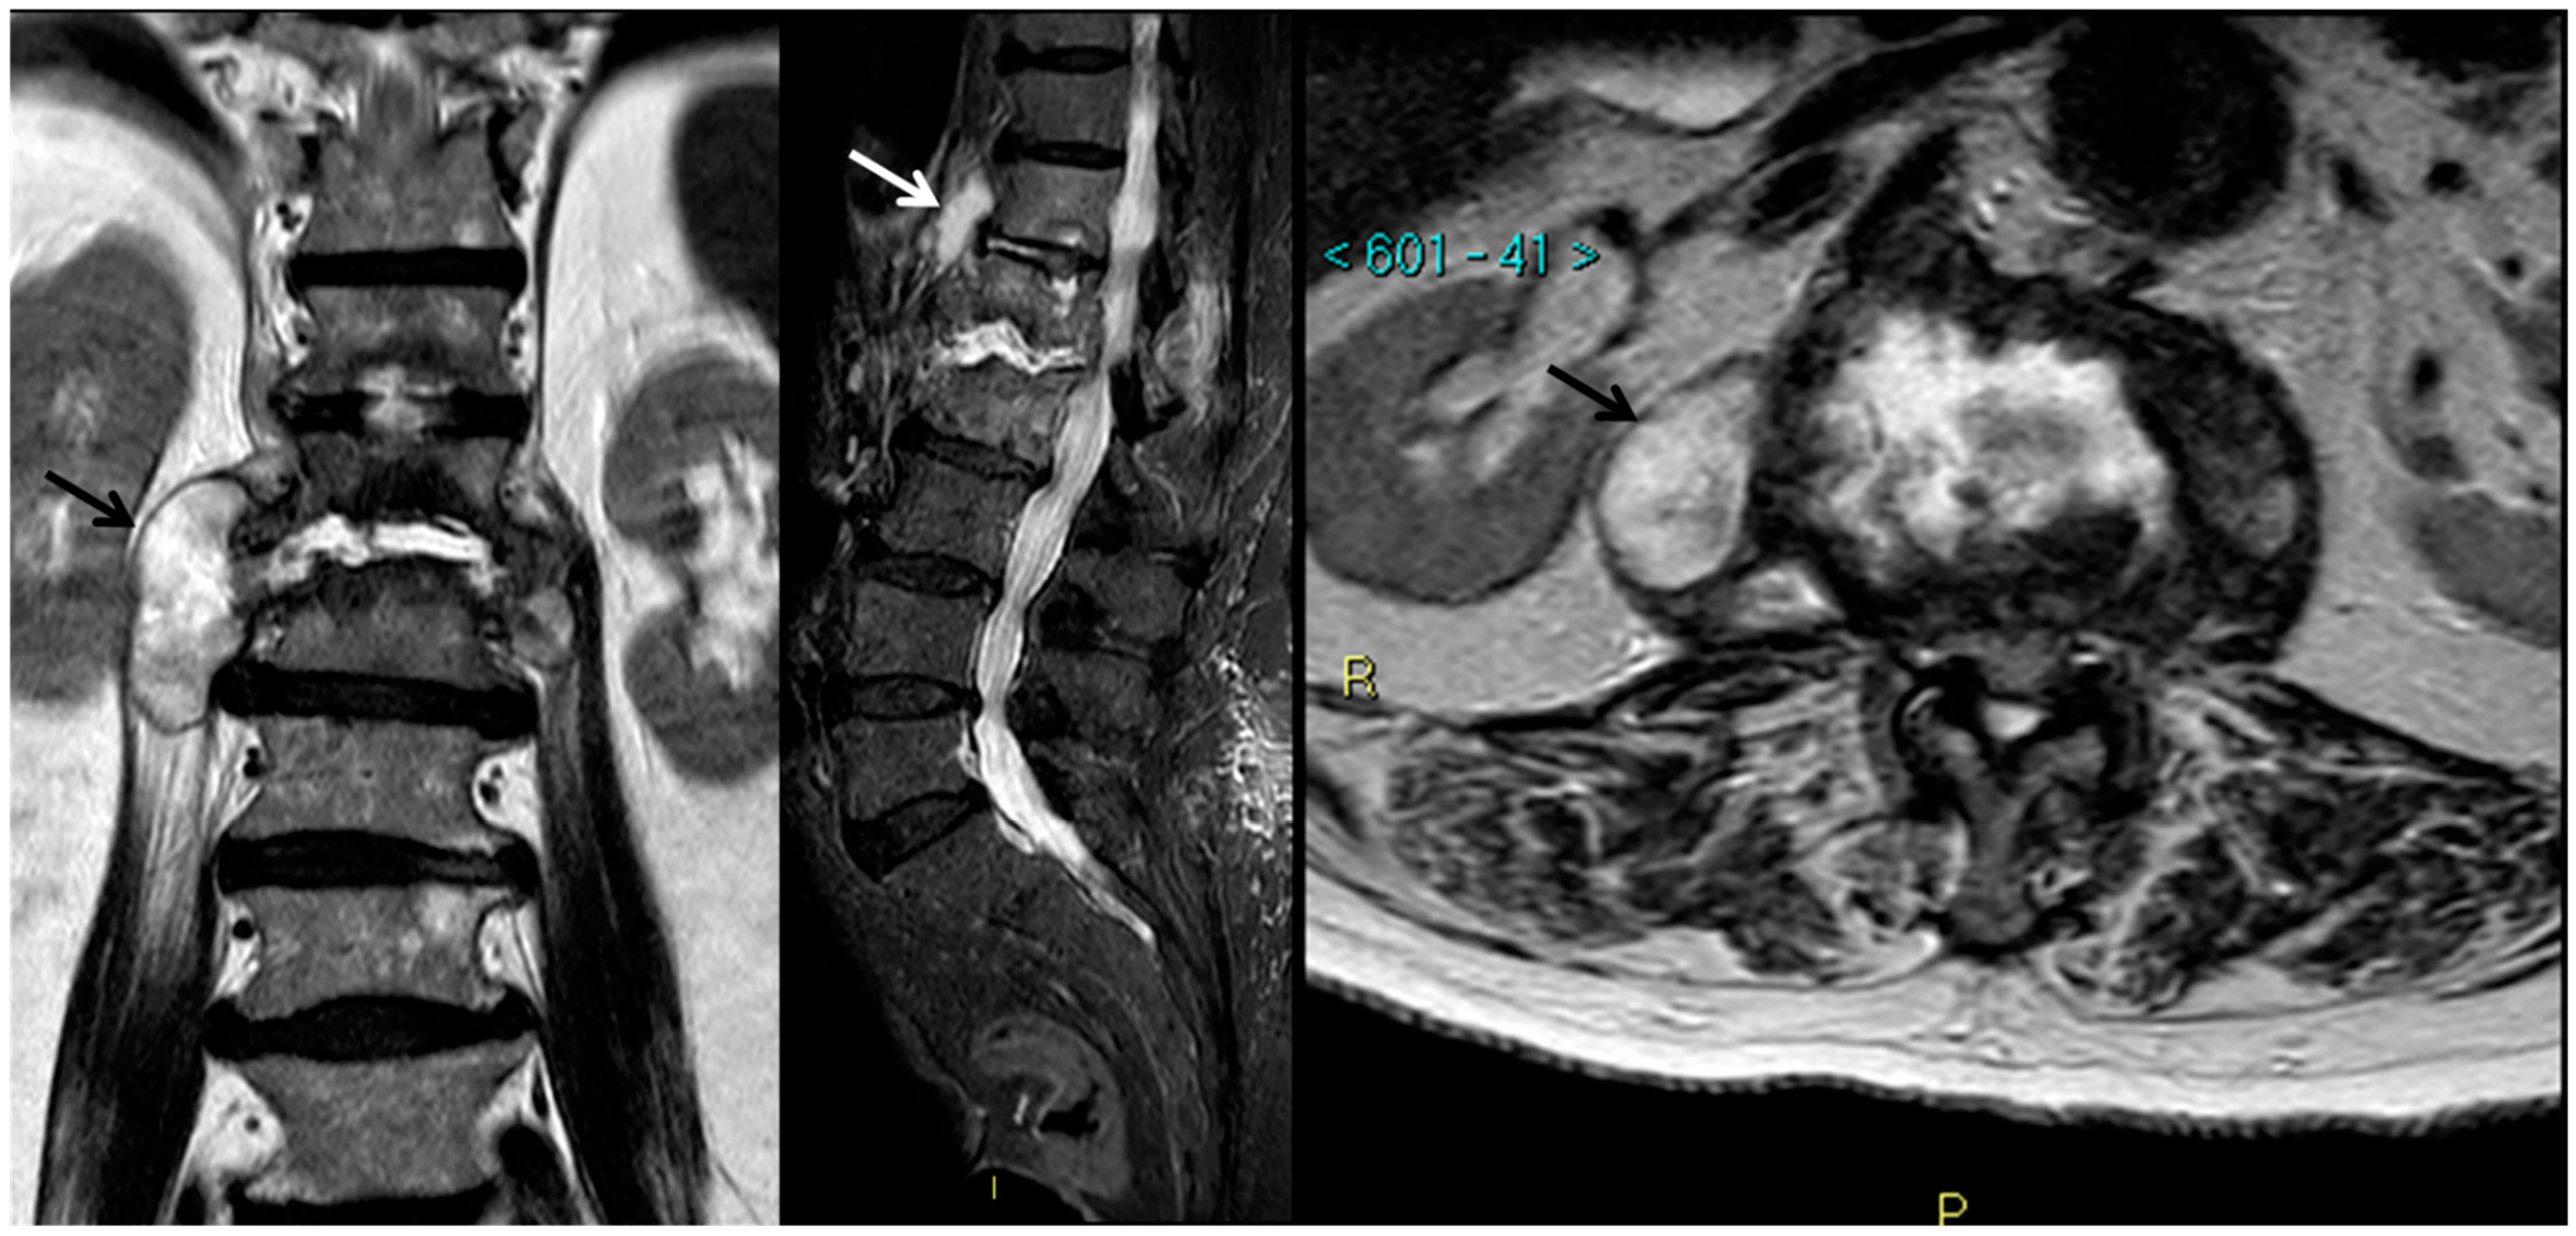

- Michel, S.C.; Pfirrmann, C.W.; Boos, N.; Hodler, J. CT-guided core biopsy of subchondral bone and intervertebral space in suspected spondylodiskitis. AJR Am. J. Roentgenol. 2006, 186, 977–980. [Google Scholar] [CrossRef] [PubMed]

- Jevtic, V. Vertebral infection. Eur. Radiol. 2004, 14 (Suppl. 3), E43–E52. [Google Scholar] [CrossRef]

- Morales, H. Infectious Spondylitis Mimics: Mechanisms of Disease and Imaging Findings. Semin. Ultrasound CT MR 2018, 39, 587–604. [Google Scholar] [CrossRef] [PubMed]

- Dumont, R.A.; Keen, N.N.; Bloomer, C.W.; Schwartz, B.S.; Talbott, J.; Clark, A.J.; Wilson, D.M.; Chin, C.T. Clinical Utility of Diffusion-Weighted Imaging in Spinal Infections. Clin. Neuroradiol. 2019, 29, 515–522. [Google Scholar] [CrossRef] [PubMed]

- Naselli, N.; Facchini, G.; Lima, G.M.; Evangelisti, G.; Ponti, F.; Miceli, M.; Spinnato, P. MRI in differential diagnosis between tuberculous and pyogenic spondylodiscitis. Eur. Spine J. 2021. [Google Scholar] [CrossRef]